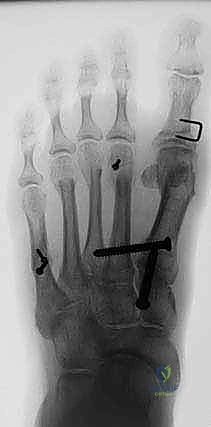

- يتم تحديد مواقع المسامير أو الشرائح المعدنية من الجراحة السابقة وإزالتها (Hardware Removal). قد تكون هذه الخطوة صعبة إذا نما العظم فوق المسامير.

أ. إعادة القطع العظمي (Revision Osteotomy - Scarf or Chevron)

إذا كان الفشل ناتجًا عن تصحيح غير كافٍ في الجراحة الأولى، وكان المفصل لا يزال سليمًا (لا توجد خشونة شديدة)، يقوم الدكتور هطيف بإجراء قطع عظمي جديد (مثل تقنية Scarf أو Chevron) لإعادة توجيه العظم وتثبيته بمسامير تيتانيوم حديثة لا تسبب تهيجًا.

ب. عملية لابيدوس (Lapidus Procedure - TMTJ Arthrodesis)

إذا كان سبب التكرار هو "فرط الحركة" في مفصل منتصف القدم (TMTJ)، فإن الحل الوحيد لمنع التكرار المستقبلي هو دمج (إيثاق) هذا المفصل. يزيل الدكتور هطيف الغضروف من المفصل، يصحح زاوية العظم، ويثبته بشريحة معدنية قوية ومسامير حتى يلتحم العظمان معًا. هذه العملية تعالج أصل المشكلة من الجذور.

ج. إيثاق مفصل المشط السلامي الأول (First MTPJ Arthrodesis)

يُعتبر هذا الإجراء "المعيار الذهبي" (Gold Standard) وجراحة الإنقاذ النهائية في حالات المراجعة المعقدة، خاصة إذا كان المريض يعاني من:

* تدمير المفصل أو خشونة شديدة (التهاب المفاصل العظمي).

* فقدان عظمي كبير من الجراحة السابقة.

* تكرار شديد للتشوه مصحوب بألم مبرح.

في هذه العملية، يتم إزالة الغضروف التالف من مفصل الإصبع الكبير، ودمج العظام معًا في وضع مستقيم قليلاً للأعلى للسماح بالمشي الطبيعي. يتم التثبيت باستخدام شريحة ومسامير متقاطعة. النتيجة هي إصبع مستقيم، خالٍ تمامًا من الألم، ولا يمكن أن يعود للتشوه أبدًا.